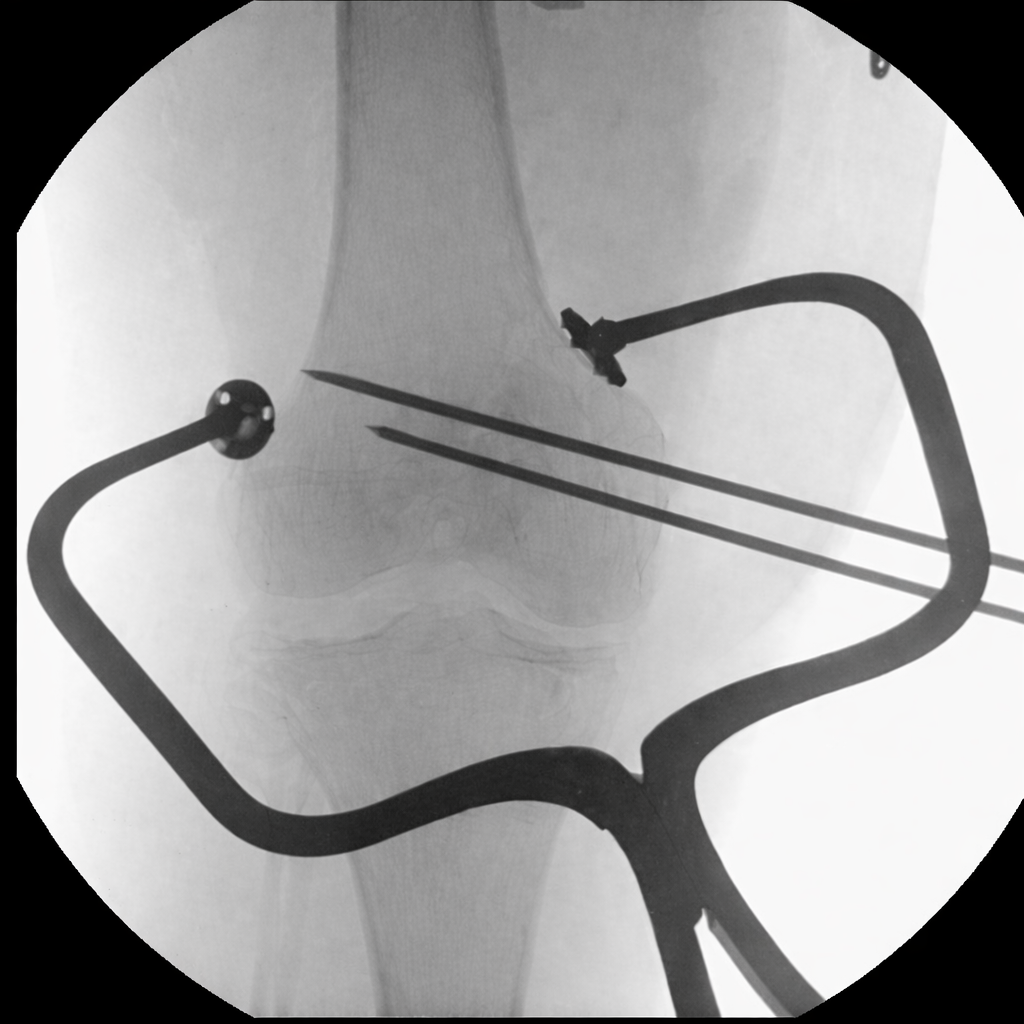

AXIA Orthopedics is developing a new solution for fracture fixation with unmatched reliability, simplicity, and versatility.

Axia's patented Reduction system:

• Works with existing surgeon flow and training

• Integrates with any implant system

• Provides precise compression of fractures and fusions

• Allows for in situ implant contouring to fit the bone

• Enables minimally invasive reduction

• Saves critical OR time

• Reduces the need for extra hands